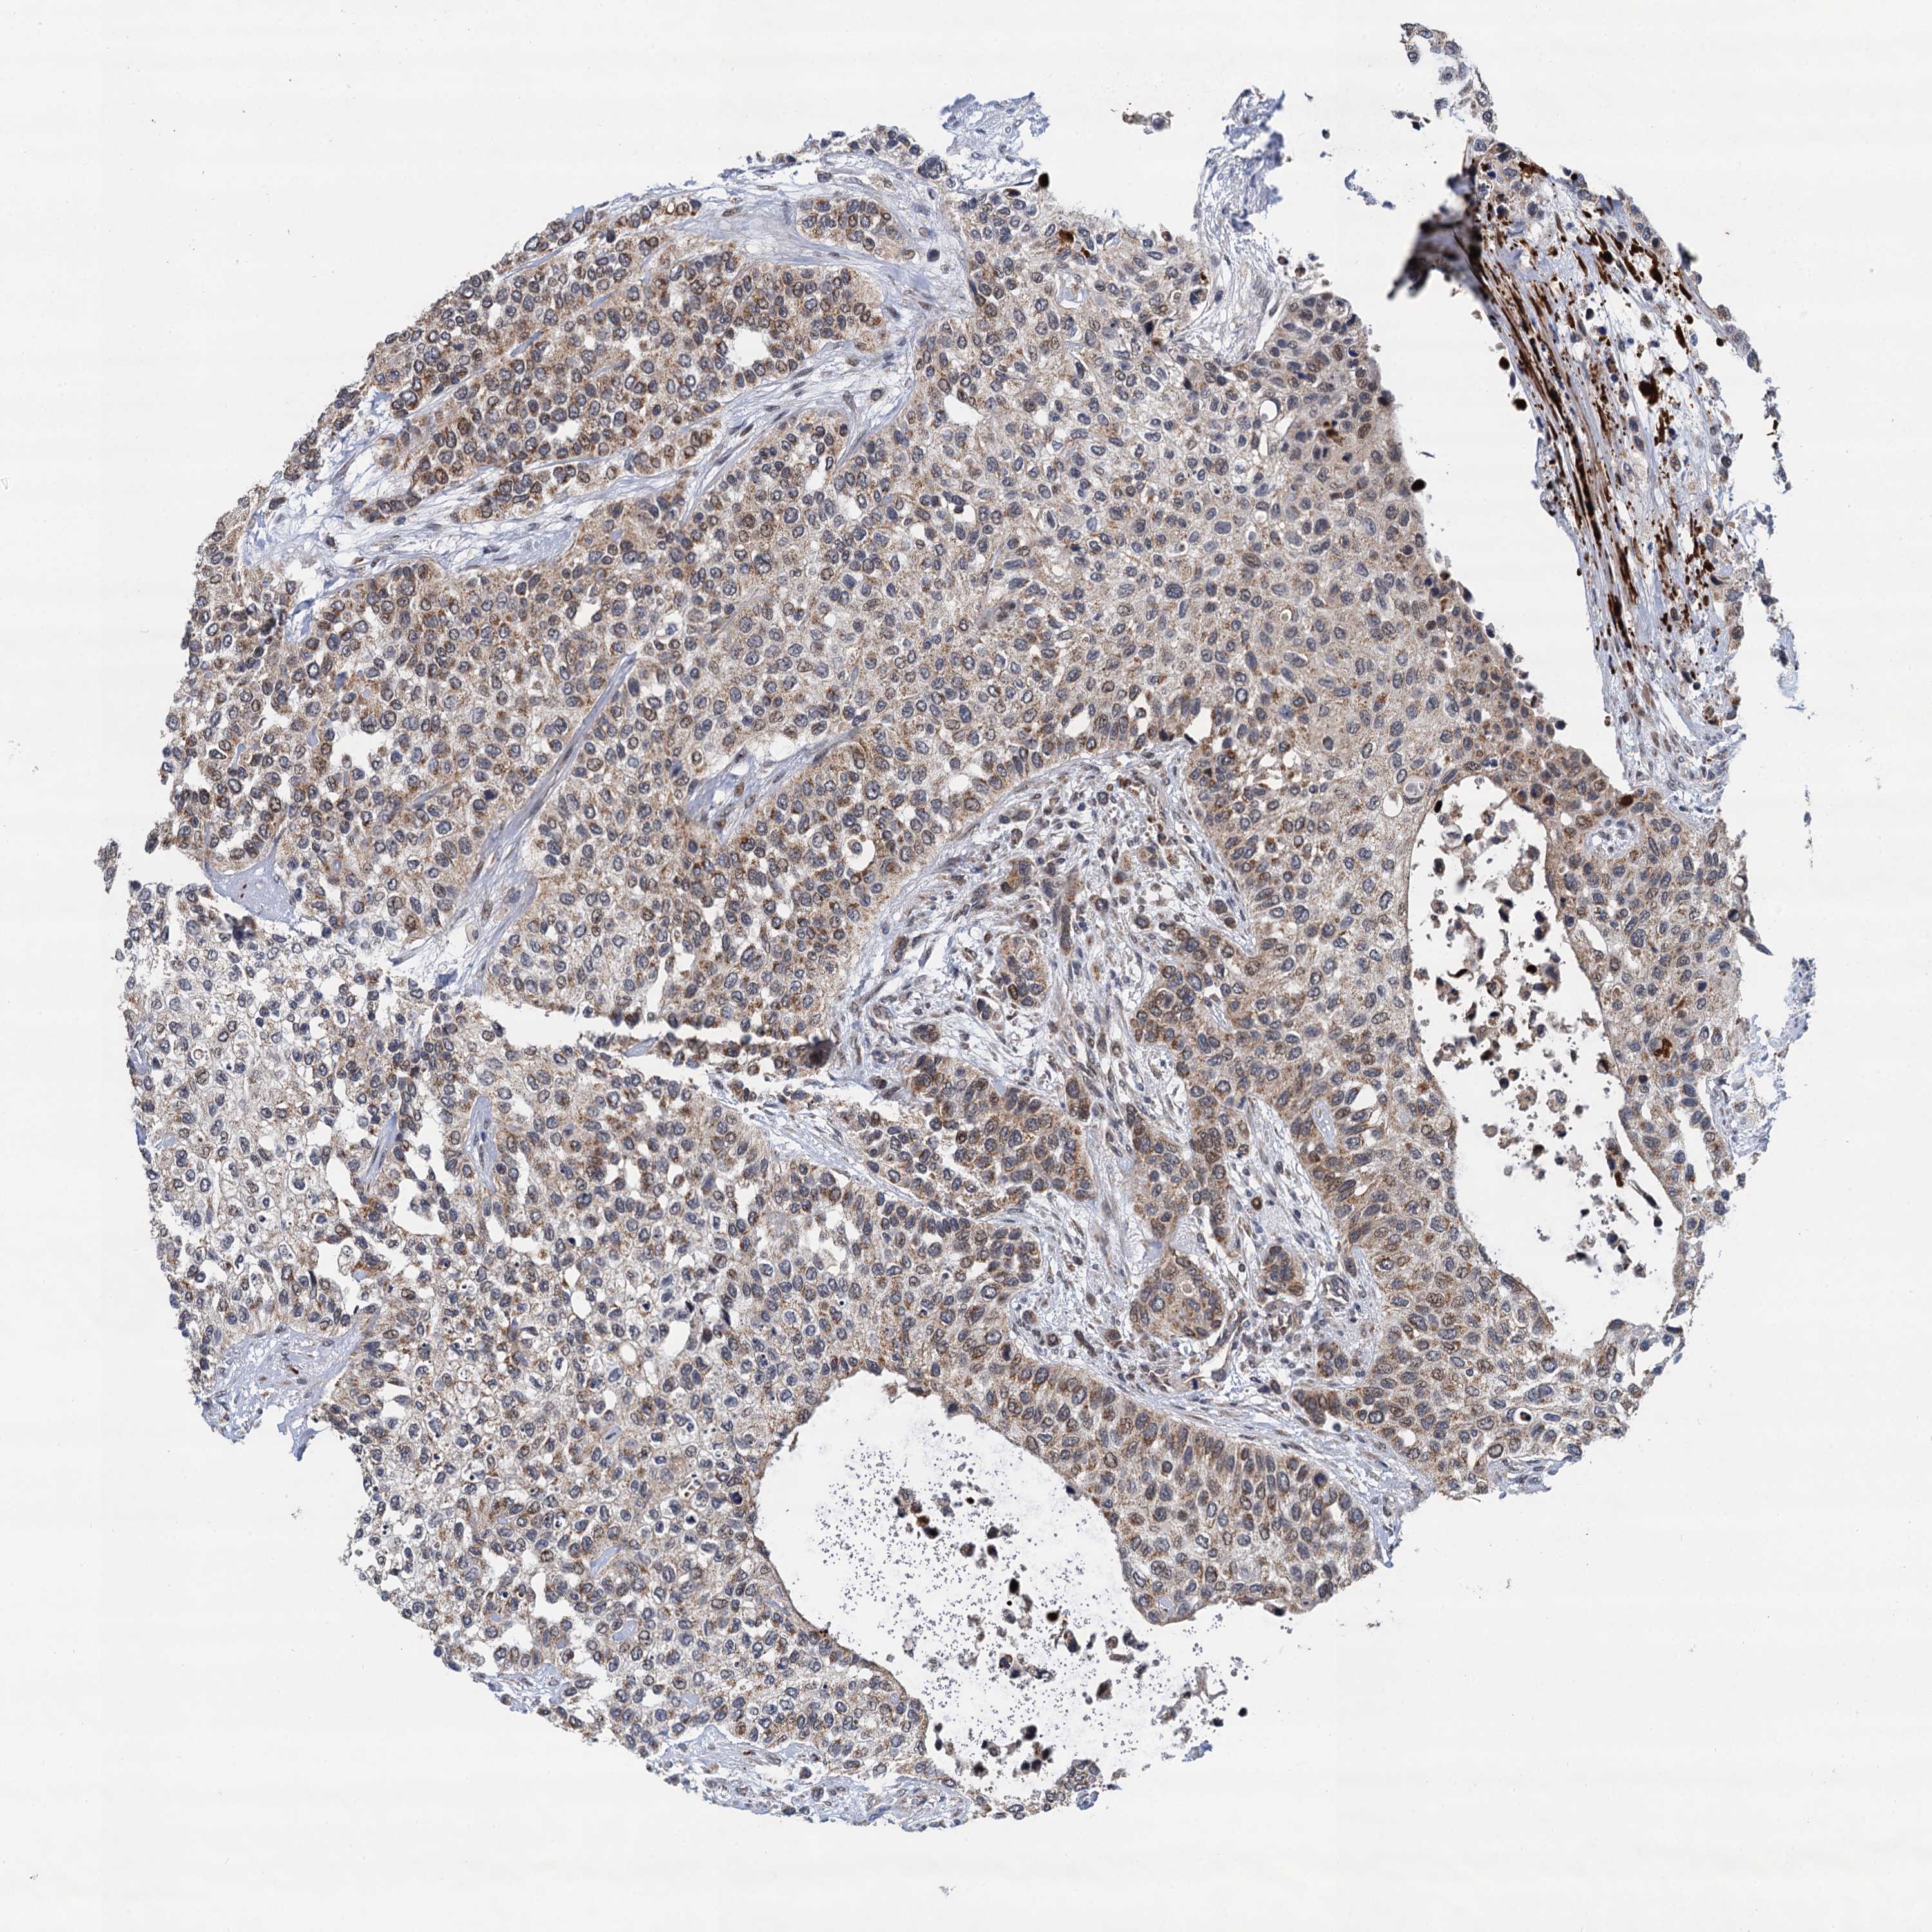

UROTHELIAL CANCER - Protein expressioni

A mouse-over function shows sample information and annotation data. Click on an image to view it in a full screen mode. Samples can be filtered based on level of antibody staining by selecting one or several of the following categories: high, medium, low and not detected. The assay and annotation is described here.

Antibody stainingi

Antibody staining in the annotated cell types in the current human tissue is reported as not detected, low, medium, or high, based on conventional immunohistochemistry profiling in selected tissues. This score is based on the combination of the staining intensity and fraction of stained cells.

Each image is clickable and will lead to virtual microscopy that enables deeper exploration of all samples and also displays staining intensity scores, fraction scores and subcellular localization as well as patient and tissue information for each sample.

Antibody HPA041430

Antibody HPA062191

Staining

High

Medium

Low

Not detected

Intensity

Strong

Moderate

Weak

Negative

Quantity

>75%

75%-25%

<25%

None

Location

Nuclear

Cytoplasmic/membranous

Cytoplasmic/membranous,nuclear

Urothelial carcinoma, High grade

Urothelial carcinoma, Low grade